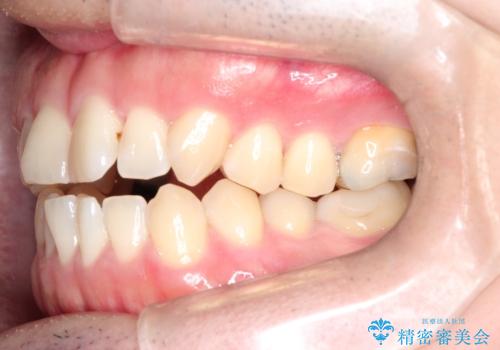

- 前歯の咬み合わせが気になるとのことで来院されました。

前歯が噛んでいない状態(開咬)のため、インビザライン矯正で改善することとしました。